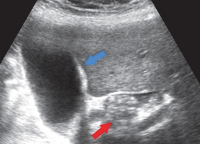

Для выявления водянки желчного пузыря в гастроэнтерологии применяются УЗИ желчного пузыря, магнитно-резонансная панкреатохолангиография, МРТ печени и желчевыводящих путей, КТ желчевыводящих путей, МСКТ органов брюшной полости. При проведении этих методик исследования обнаруживается увеличенный в размерах желчный пузырь с истонченными стенками, неоднородное содержимое в его полости; могут быть конкременты, как в пузыре, так и в желчных путях. Также могут выявляться другие причины обструкции выхода из желчного пузыря: опухоли, спайки, рубцовые стриктуры.